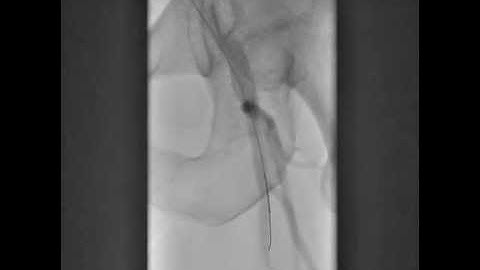

Case 19: Manual of CTO Interventions - CrossBoss for in-stent CTO